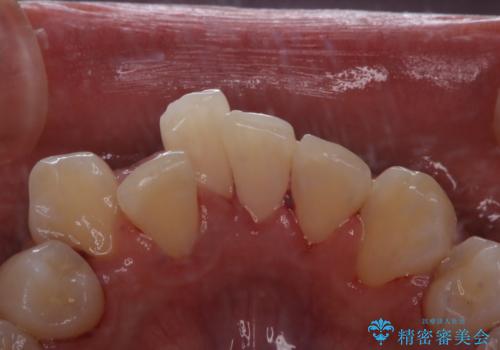

ホワイトニング

ホワイトニングは、歯を削ったり、傷つけたりすることなく歯の内部の象牙質まで浸透し、色素を分解して漂白することで、くすることができます。

ホワイトニングには歯科医院で行うオフィスホワイトニングと、ご自宅で行うホームホワイトニングがあります。

当法人ではプラン内容が細かく分かれていますので、ご自身に合わせたホワイトニングプランを立てることができます。